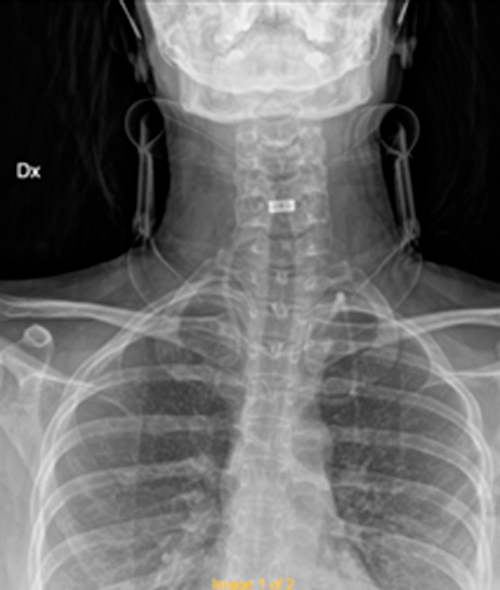

DIAGNOSI:

Ernia discale cervicale c5-c6

Risonanza magnetica cervicale pre-operatoria

Intervento chirurgico eseguito:

Microdiscectomia cervicale con approccio anteriore + introduzione di cage intersomatica cervicale

Radiografia cervicale post-operatoria